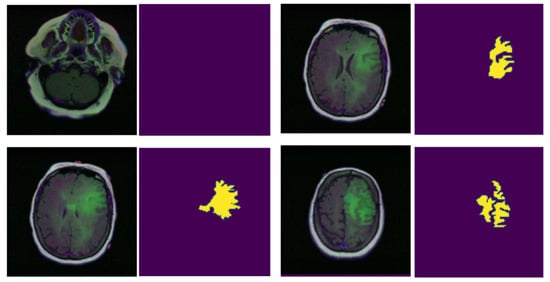

4.1. Experimental Dataset

- Optimal Architecture Depth: The MPB-UNet, with its three encoder and decoder stages, strikes an ideal balance between model complexity and feature extraction capability. Unlike shallower models, which may struggle to capture complex features, or deeper models, which might be prone to overfitting, the MPB-UNet achieves the optimal depth for this task.

- Efficient Feature Extraction: The multi-parallel block structure in the MPB-UNet allows for the efficient extraction of features at multiple scales. This is particularly beneficial for brain tumor segmentation, where tumors can vary significantly in size and shape.

- Reduced Overfitting: Compared with more complex models, the MPB-UNet has fewer parameters, which helps in reducing overfitting, especially given the limited size of most medical imaging datasets. This is evidenced by its consistent performance across both training and test sets.